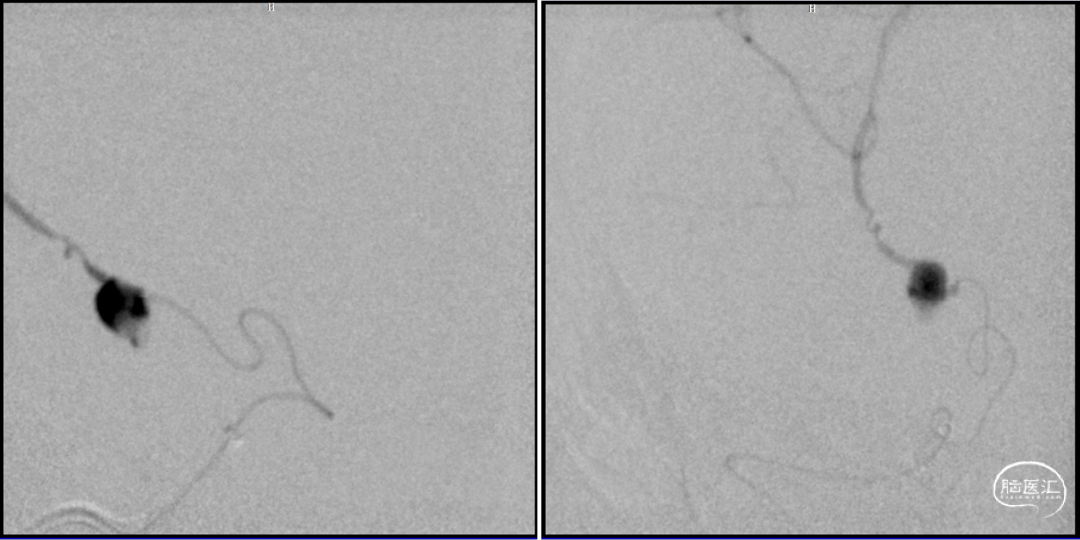

DSA

2023-08-30

前后循环3d融合寻找假性动脉瘤供血,

考虑为后交通动脉

1.右侧后交通动脉远端假性动脉瘤;